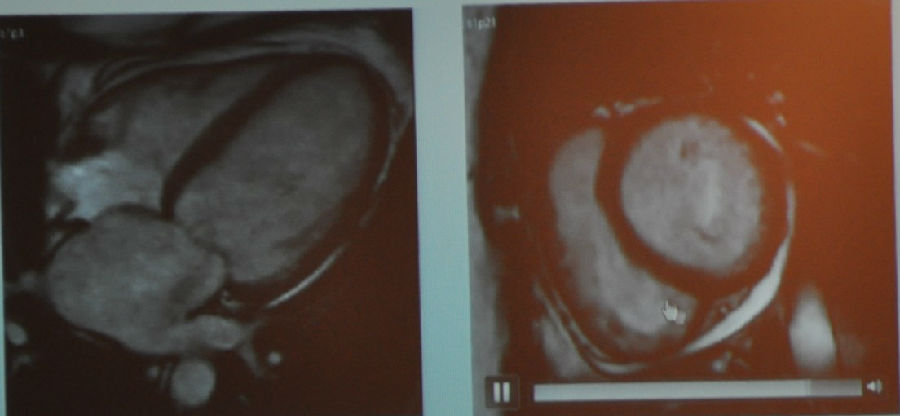

图5 MR成像(LVEF=48%,左室质量159g/m2)

严重的向心性肥厚,心壁厚度2.4cm(正常值<1.2cm)。可以看到周围白色的区域是心包积液,至少是中度的。此外尚有右心严重肥厚,厚度>1cm。

图6 MR增强(从左到右依次为四腔心切面、短轴切面)

刚才已经讲过黑色部分是正常的心肌组织,那么我们可以从该患者的MR增强图中看到整个心脏都是重度弥散性的增强,已经没有正常的心肌组织了。

图7 T1加权像

图8-9 左:增强图像 右:刚果红染色

我们接着进一步做了定量检查,最终患者被诊断为心脏淀粉样变。这样的疾病在临床上是比较难以诊断的,除非做活检。最终这名患者还是做了活检。这类疾病的确诊对患者治疗方案的制定是有明显的指导作用的,患者后续可以针对淀粉样变做进一步的治疗而不是单纯地只治疗心衰。